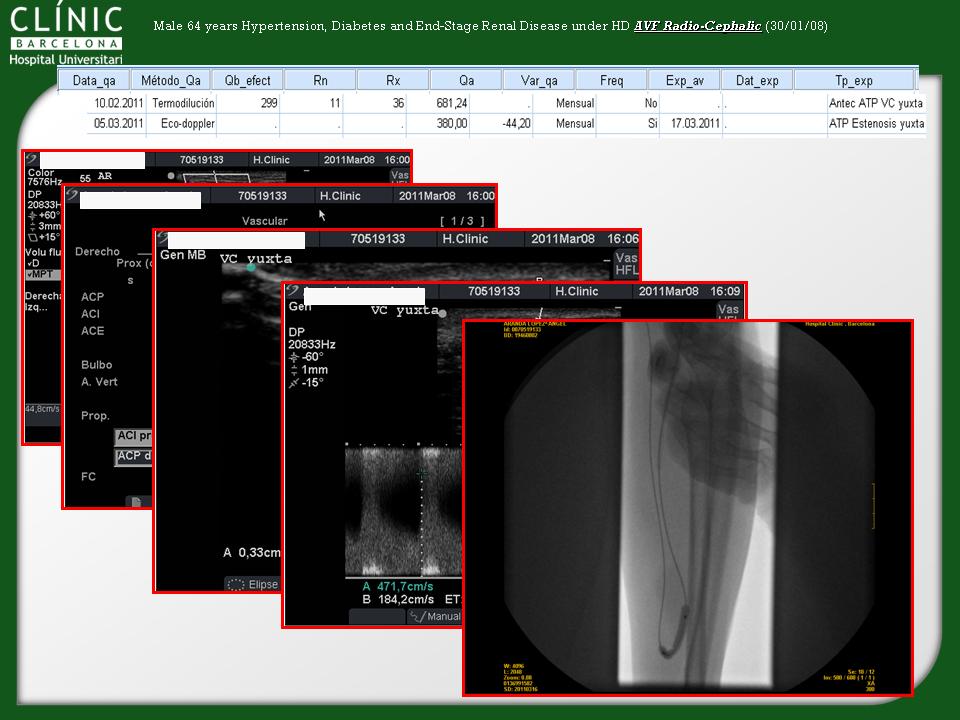

Time and criteria for fistula maturation

Dr. Fontseré